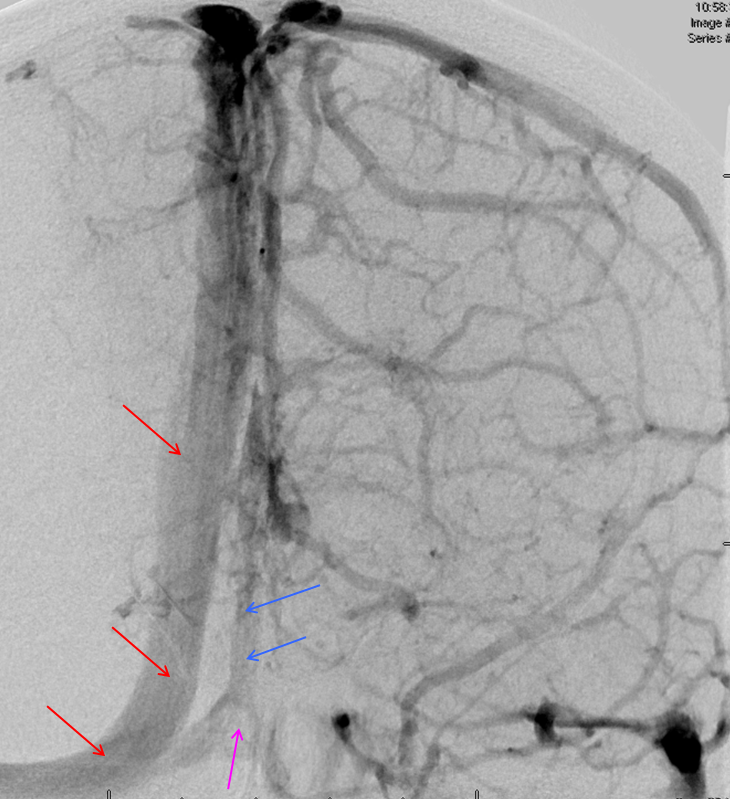

Below is an example of as large an inferior sagittal sinus (white) as one is likely to ever see under non-pathologic circumstances. Why is this sinus so large? Again, the answer is that veins are like rivers — the inferior sagittal sinus happens to be receiving a completely benign, nonpathologic mesial anterior frontal vein (blue arrows). However, the increased inflow into the Galen system has likely resulted in alternate drainage of the basal vein (purple) into the superior petrosal sinus via the lateral mesencephalic vein (black) — see deep venous system and veins of posterior fossa pages for more info. Also notice a large emissary vein (pink)